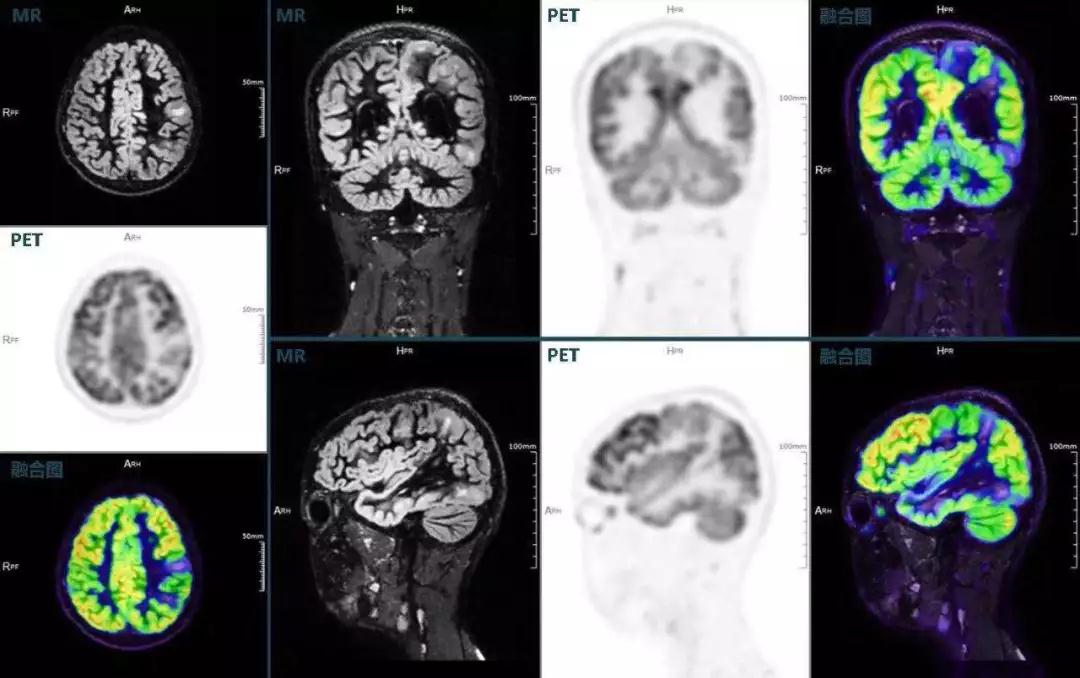

癲癇

不僅如此,聯(lián)影“時空一體”超清TOF PET/MR還搭載了大量可用于神經(jīng)疾病領(lǐng)域的高級應(yīng)用,如DIR(Double Inversion Recovery雙反轉(zhuǎn)恢復(fù))序列能夠清晰顯示大腦皮層的結(jié)構(gòu)成像,對于皮層腫脹,膠質(zhì)增生等癲癇的影像征象都能清楚呈現(xiàn);DTI(Diffusion Tensor Imaging彌散張量成像)高級應(yīng)用能夠顯示細(xì)小的神經(jīng)纖維束缺損,以更加定量的形式為醫(yī)生提供一個全新的診斷維度,輔助醫(yī)生精準(zhǔn)診斷。

(結(jié)節(jié)性硬化,MR DIR序列清晰顯示腦皮層病理改變,PET顯示了病灶區(qū)域FDG的低濃聚。PET/MR融合顯像同時提供了結(jié)構(gòu)異常改變和功能變化的信息。)